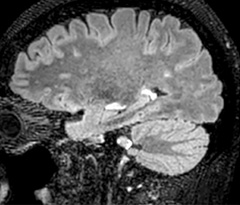

A two year follow-up scan of a CPA meningioma using both Ingenia 3.0T without CS and Ingenia Elition 3.0T with Compressed SENSE allows for a nice comparison to demonstrate the protocol improvements achieved on the Elition: 3D FLAIR has a shortened scan time, improved SNR and still the same spatial resolution. BrainView (3D T1 TSE) has improved spatial resolution and SNR with shortened scan time. For 3D T2 Drive the spatial resolution has been improved. 3D THRIVE used to have an interpolated 0.8 mm slice thickness, but true thickness at 1.6 mm, so that axial slices displayed a decent quality, but reformats were suboptimal. Compressed SENSE is used on Elition to improve spatial resolution and reduce the non-interpolated slice thickness to allow smoothly reformatted images. Total scan time (adding SmartBrain and an additional b2000 diffusion) was 13:19 on Ingenia, and is now reduced to 10:42 on Ingenia Elition.

Ingenia 3.0T (without Compressed SENSE)

3D FLAIR 1.0 x 1.0 x 1.0 mm* 4:24 min.

3D TSE T1w 1.0 x 1.0 x 1.2 mm* 2:40 min.

3D T2w Drive 0.8 x 0.8 x 1.0 mm* 3:05 min.

3D T1w THRIVE 0.8 x 0.8 x 1.6 mm* 1:30 min.

Ingenia Elition 3.0T with Compressed SENSE

3D FLAIR 1.0 x 1.0 x 1.0 mm* 2:50 min.

3D TSE T1w 1.0 x 1.0 x 1.0 mm* 2:10 min.

3D T2w Drive 0.7 x 0.7 x 0.7 mm* 2:52 min.

3D T1w THRIVE 0.7 x 0.7 x 0.8 mm* 1:30 min.

*true voxel size, without interpolation